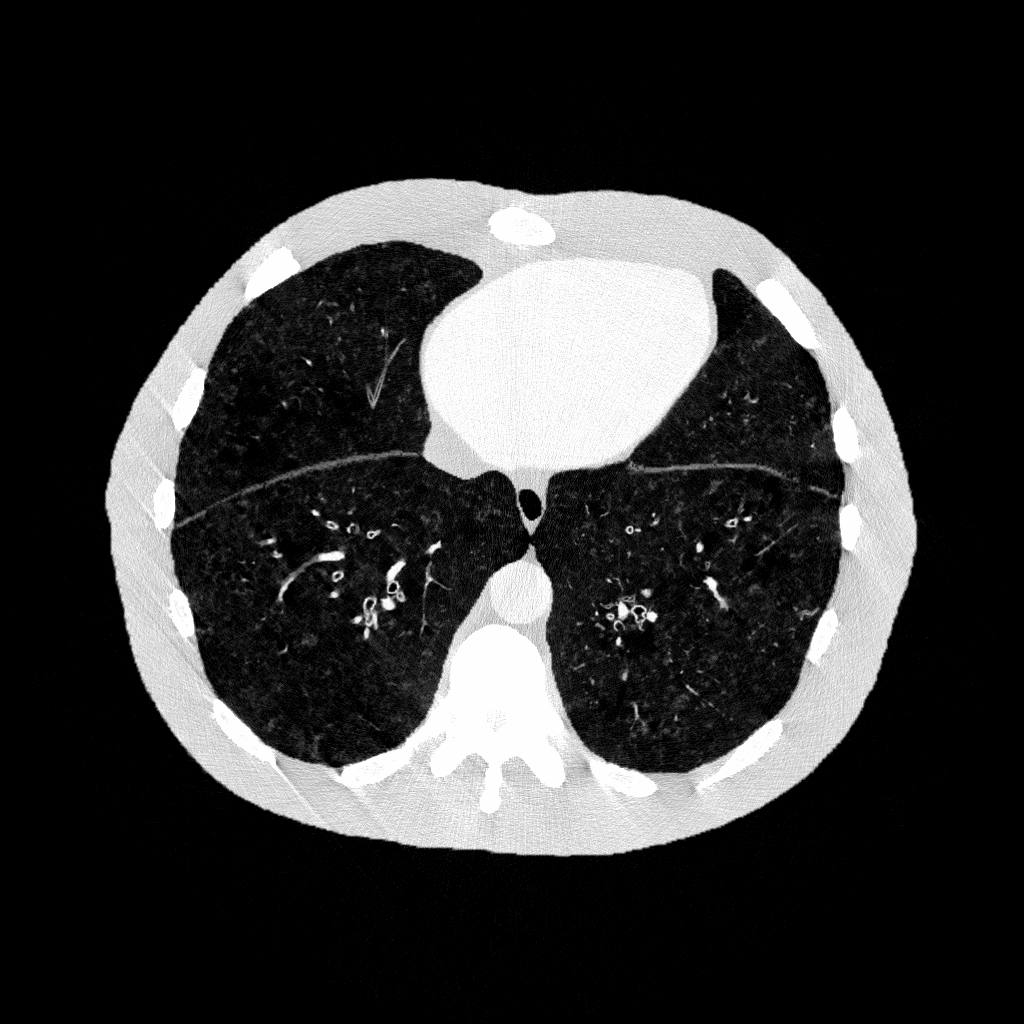

Example datasets: axial cross-sectional 3D CT images of a digital human phantom with COPD, generated using DukeCounter photon-counting CT scanners

Images from CdTe-based DukeCounter Scanner